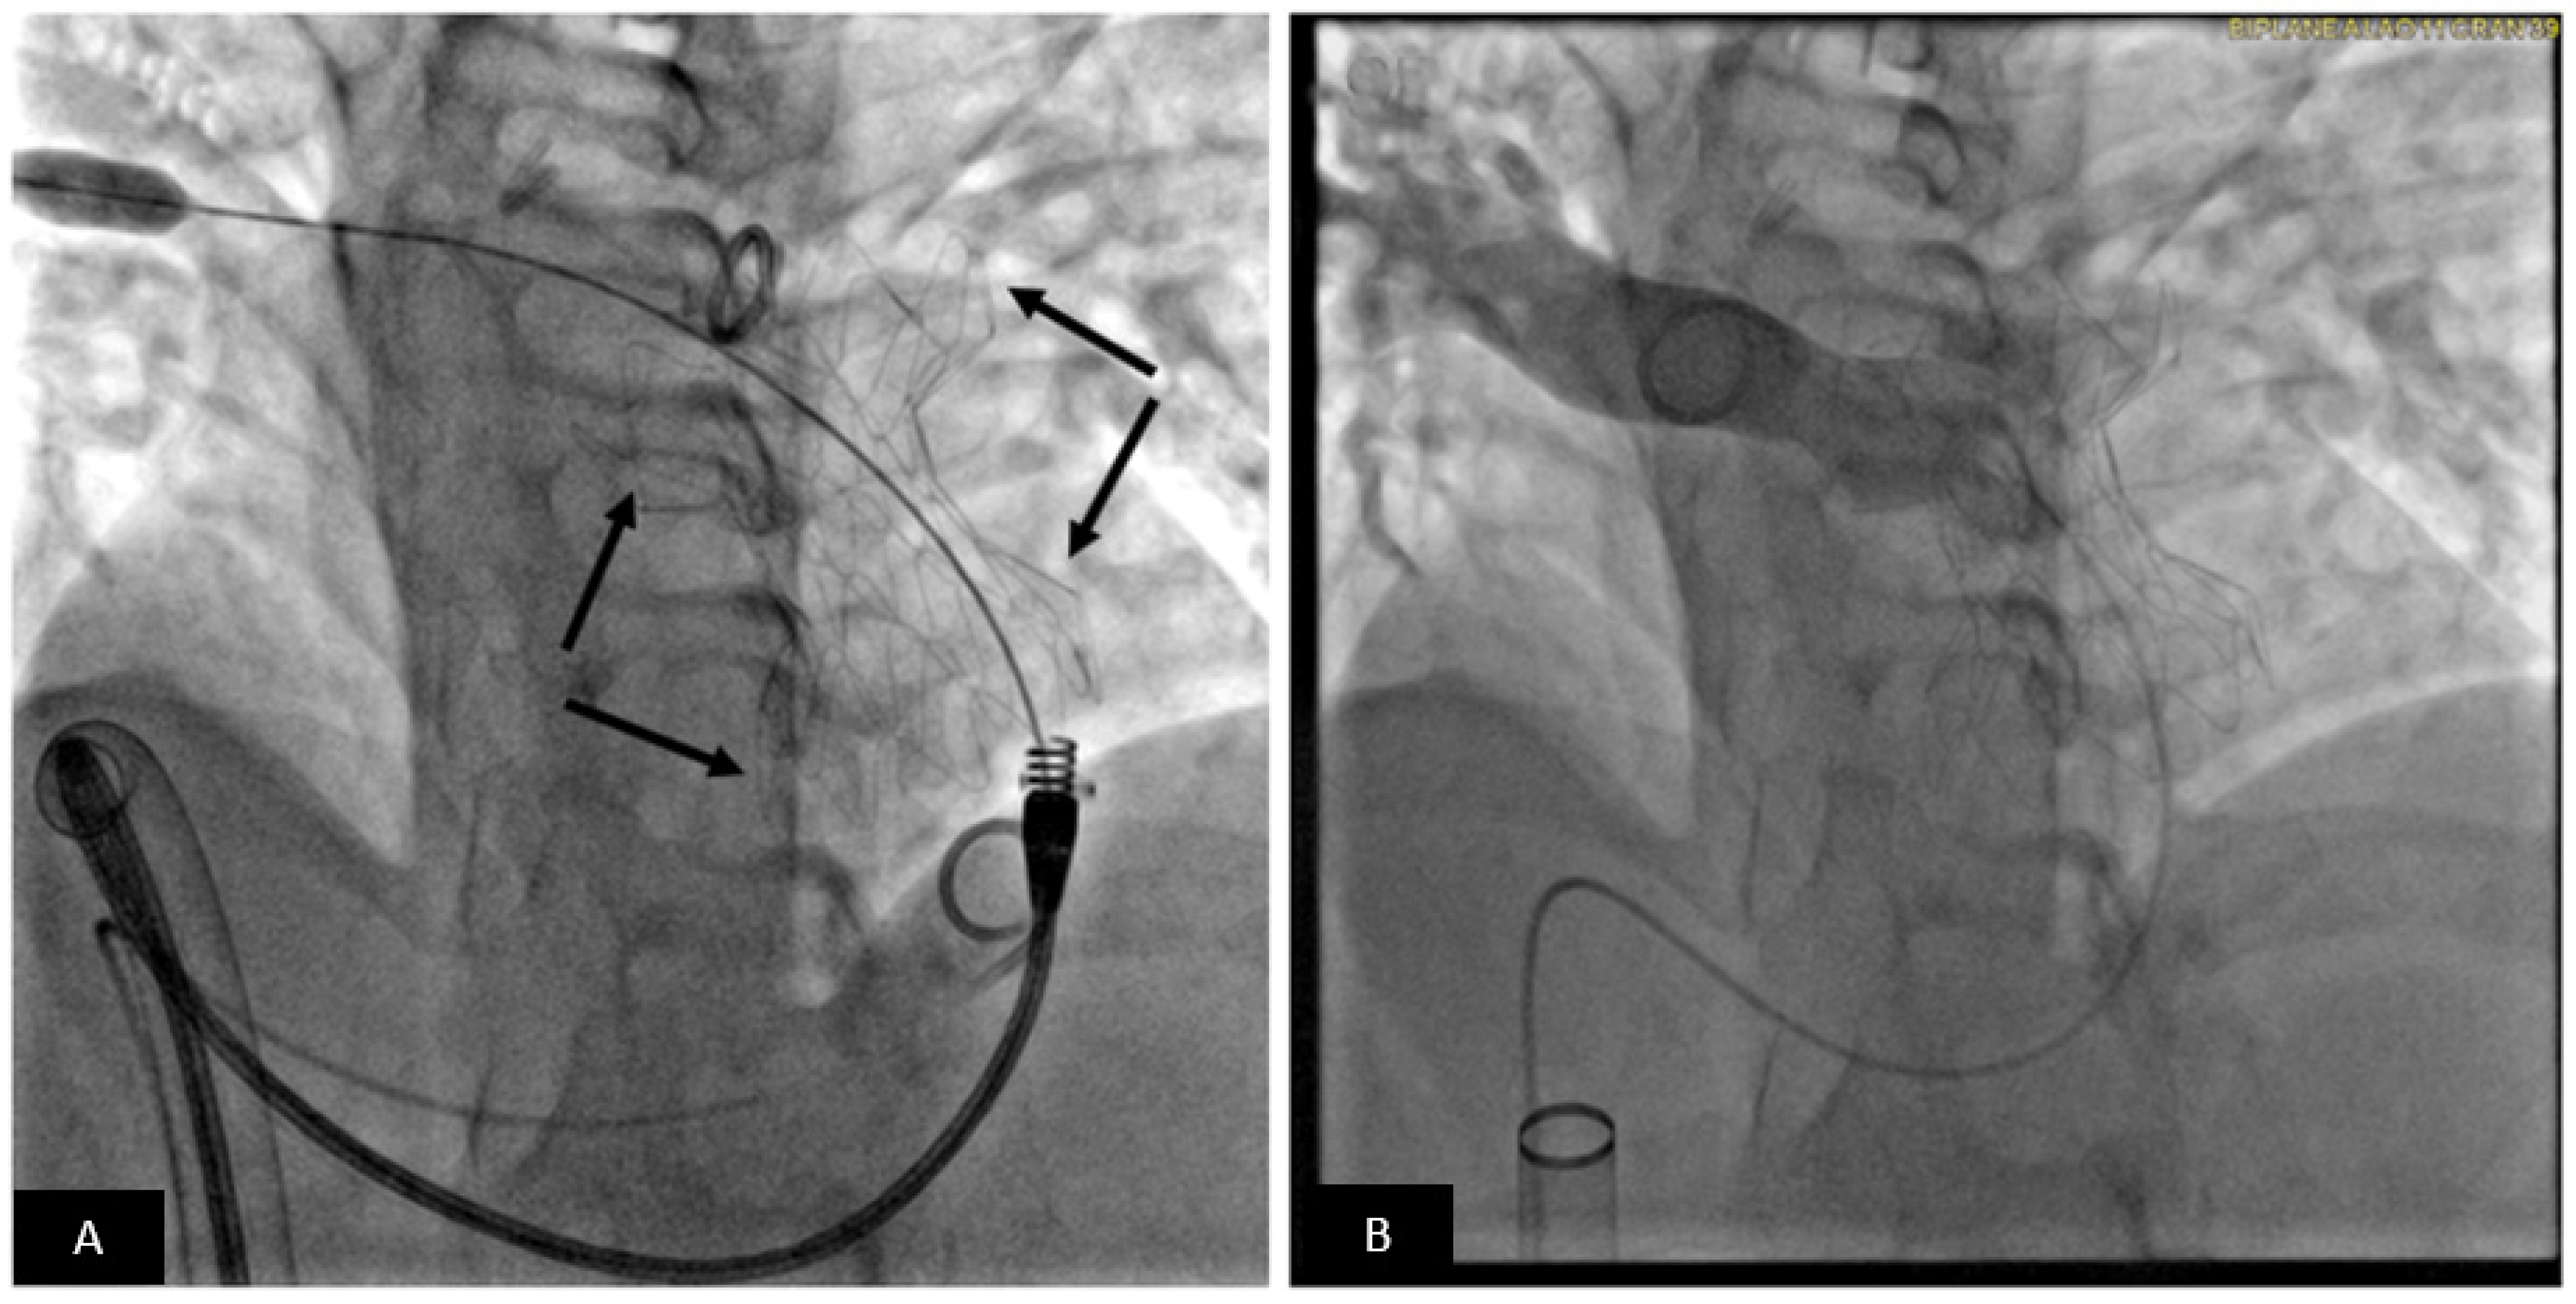

- Valverde, I.; Gomez, G.; Coserria, J.F.; Suarez-Mejias, C.; Uribe, S.; Sotelo, J.; Velasco, M.N.; Santos De Soto, J.; Hosseinpour, A.R.; Gomez-Cia, T. 3D printed models for planning endovascular stenting in transverse aortic arch hypoplasia. Catheter. Cardiovasc. Interv. 2015, 85, 1006–1012. [Google Scholar] [CrossRef] [PubMed]

- Pluchinotta, F.R.; Sturla, F.; Caimi, A.; Giugno, L.; Chessa, M.; Giamberti, A.; Votta, E.; Redaelli, A.; Carminati, M. 3-Dimensional personalized planning for transcatheter pulmonary valve implantation in a dysfunctional right ventricular outflow tract. Int. J. Cardiol. 2020, 309, 33–39. [Google Scholar] [CrossRef]